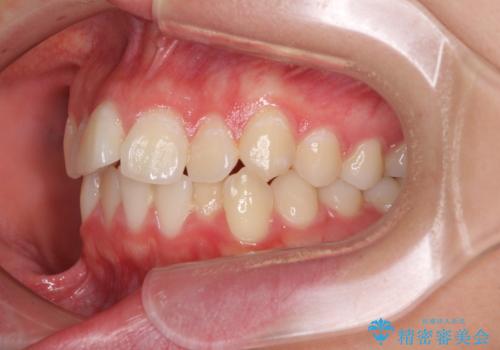

前歯のデコボコを改善 インビザライン矯正

- 口元のデコボコを気にして来院された患者様です。

前歯の捻れにより口元が閉じにくくなっていたため、歯列全体の側方への拡大と、歯と歯の間を少し削ってスペースを獲得することとしました。

ゴムかけをしっかりと行ってもらい、スッキリとした口元に仕上げることができました。